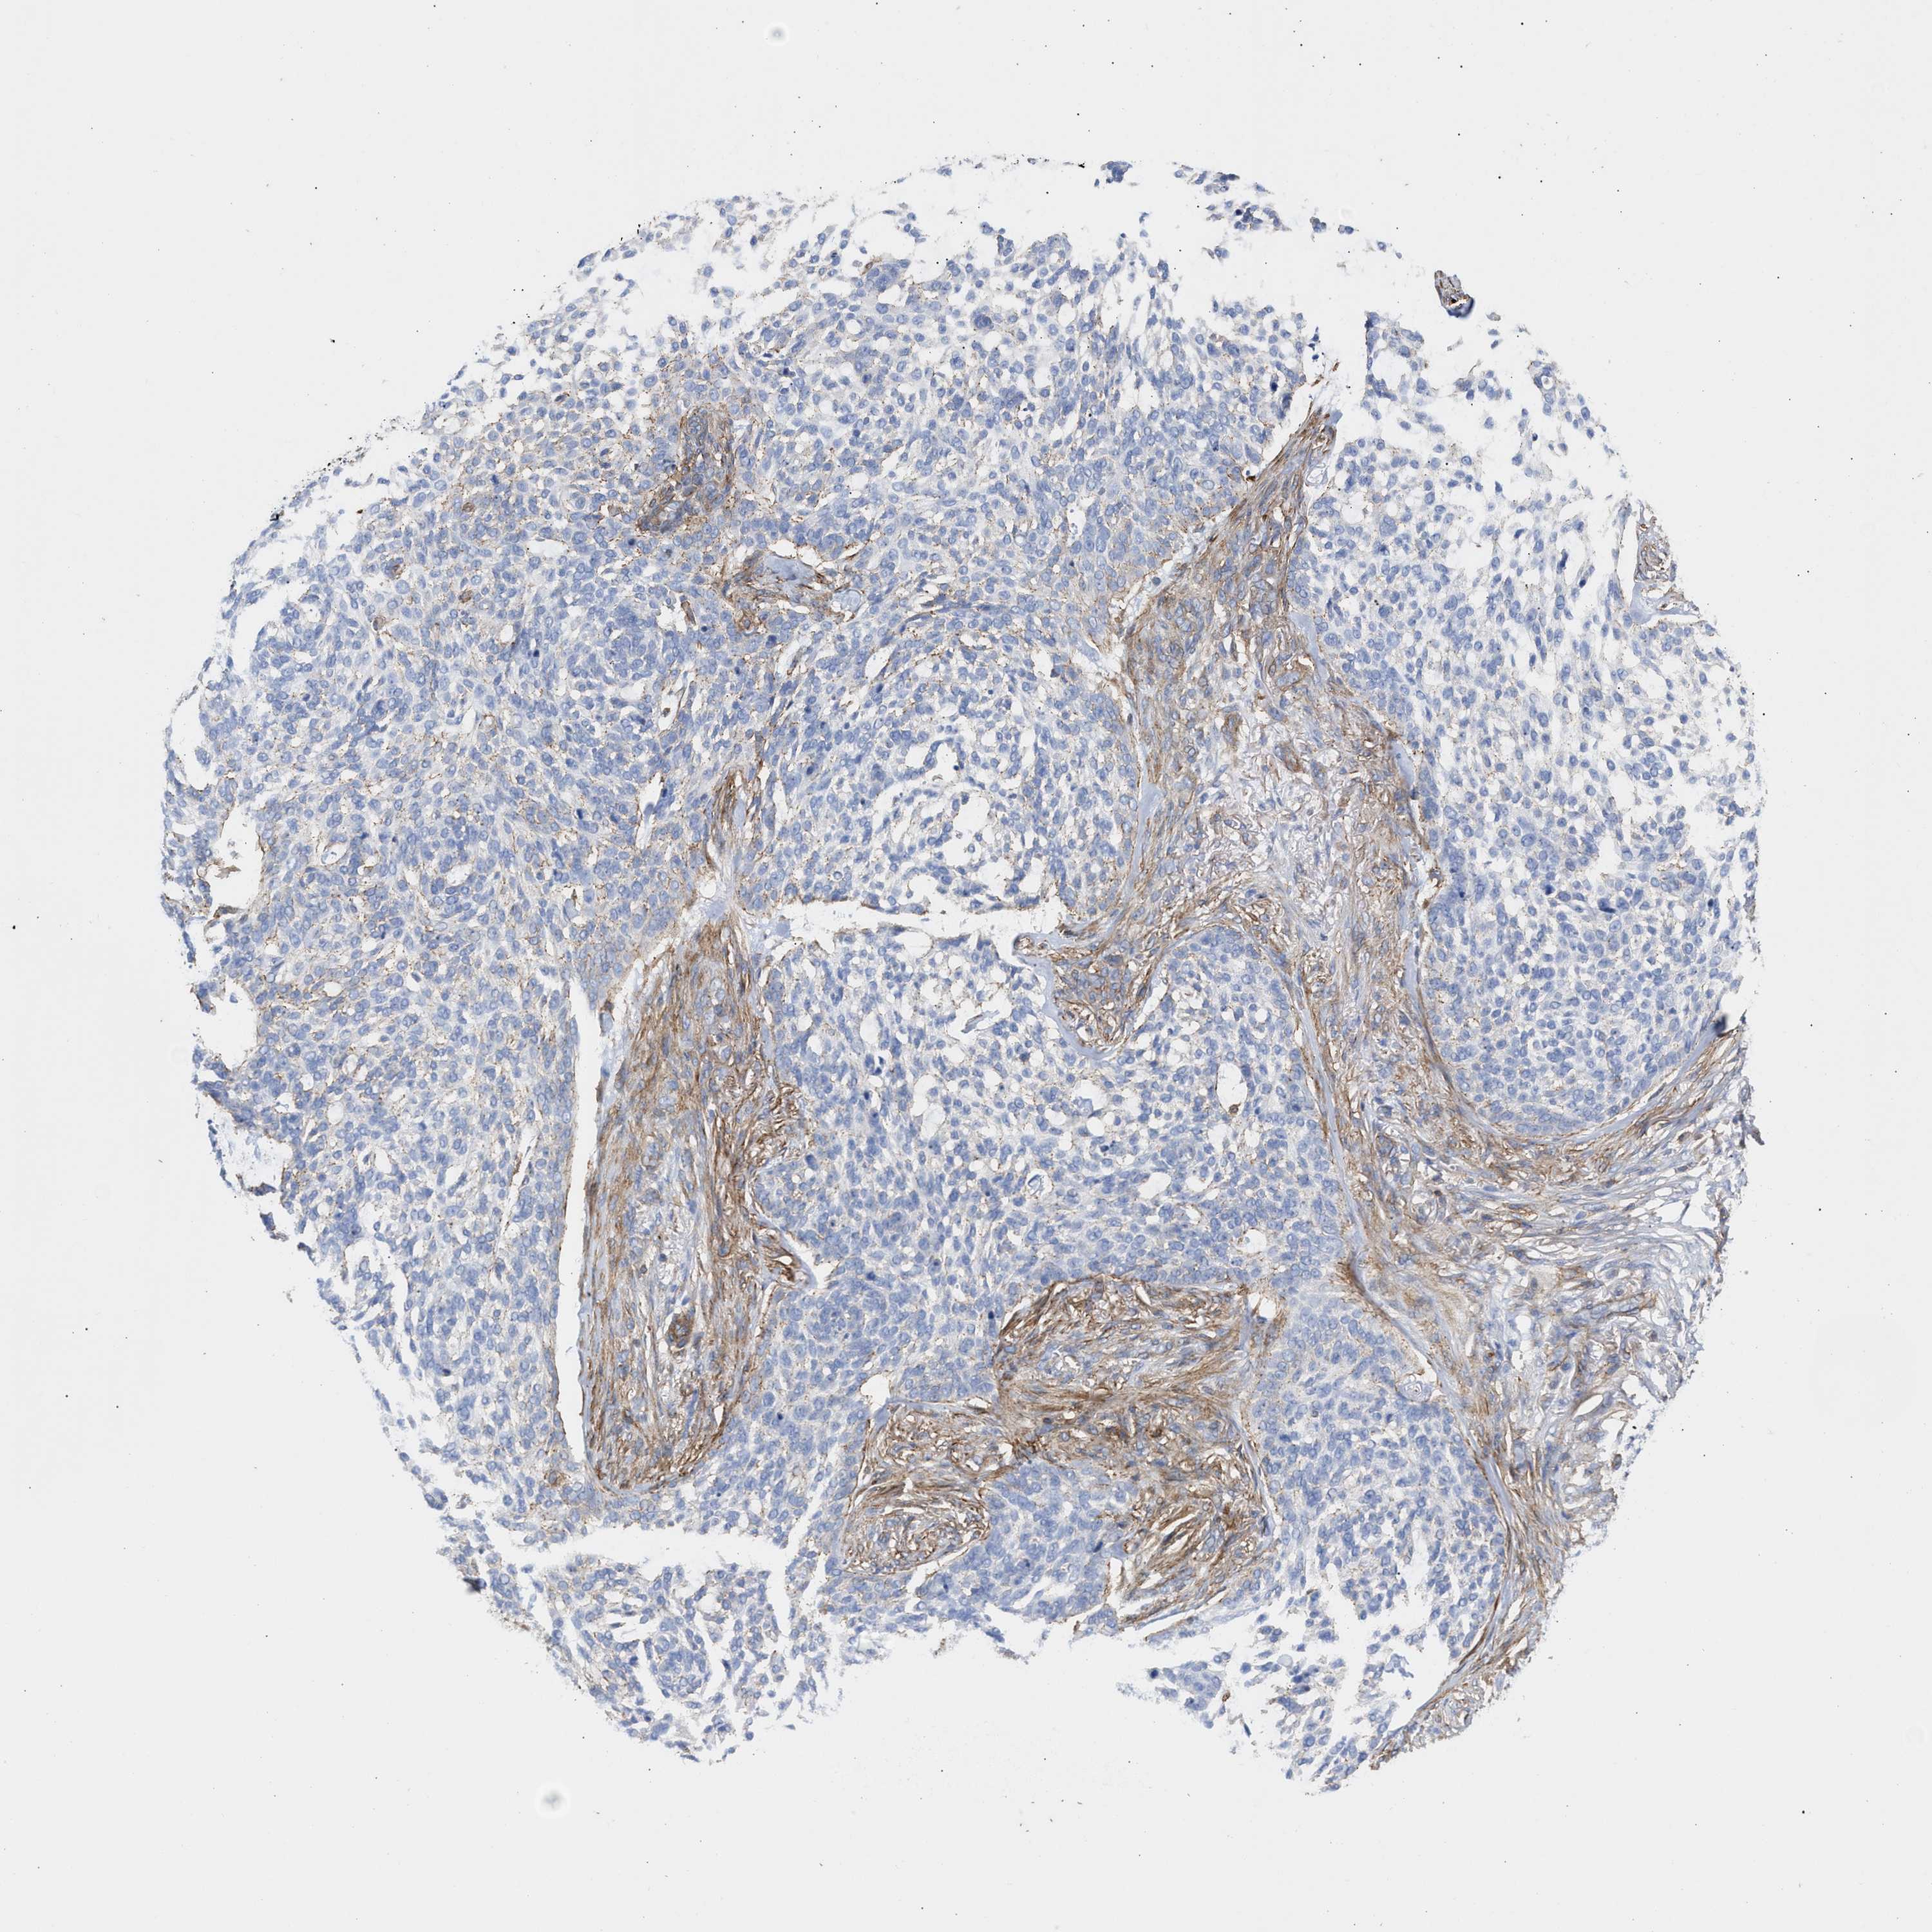

SKIN CANCER - Protein expressioni

A mouse-over function shows sample information and annotation data. Click on an image to view it in a full screen mode. Samples can be filtered based on level of antibody staining by selecting one or several of the following categories: high, medium, low and not detected. The assay and annotation is described here.

Antibody stainingi

Antibody staining in the annotated cell types in the current human tissue is reported as not detected, low, medium, or high, based on conventional immunohistochemistry profiling in selected tissues. This score is based on the combination of the staining intensity and fraction of stained cells.

Each image is clickable and will lead to virtual microscopy that enables deeper exploration of all samples and also displays staining intensity scores, fraction scores and subcellular localization as well as patient and tissue information for each sample.

Antibody HPA021823

Basal cell carcinoma

Squamous cell carcinoma, NOS

Squamous cell carcinoma, metastatic, NOS

BCC, high aggressive